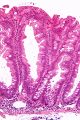

| صورة مجهرية لورم غدي مشرشر مفلح. |

Low magnification micrograph of a SSA.